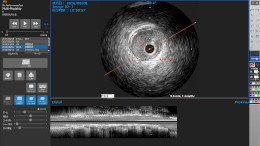

- マルティモダリティ対応(XA/US/IVUS/OCT/CT/MRI/CR/NM/DICOMPDF/SR等)

- IVUS動画像から長軸画像の生成